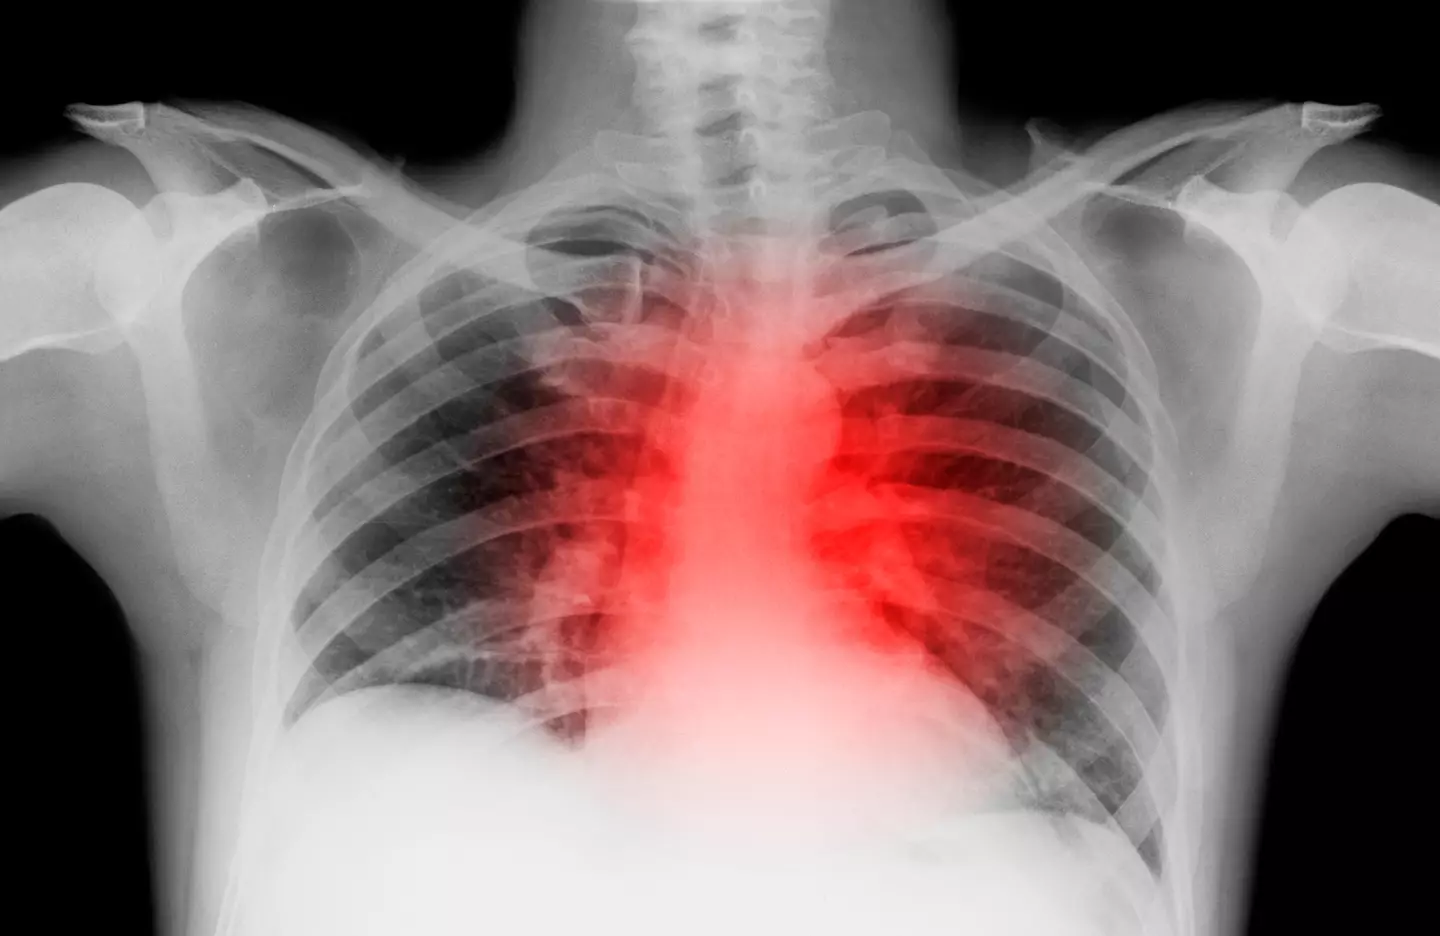

The symptom, which is similar to that of a heart attack, occurs when there is inflammation at the point your ribs join the bone in the middle of your chest (breastbone).

Costochondritis, as the condition is called, usually causes a sharp pain in the centre of the chest.

This may worsen when you move your upper body, lie down, breathe deeply, or press the middle of your chest.